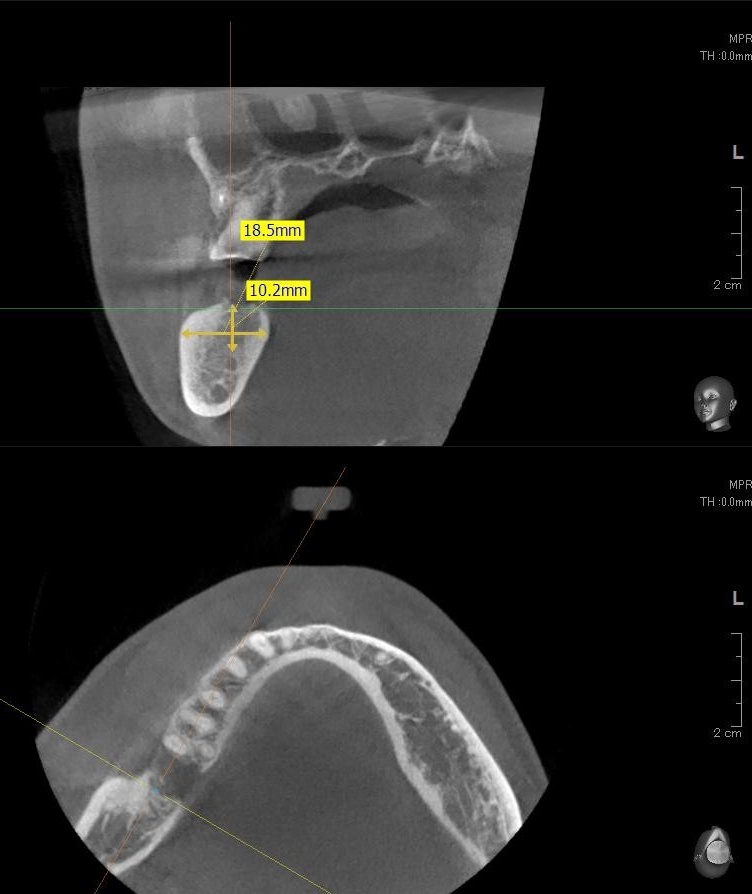

今回の患者様はインプラント植立を希望され、右下7番目の植立が決まりました。

ドリルの先端を細い物から徐々に大きい物に変えながら、植立するインプラント体のネジの部分を除いた胴の部分の太さに合わせた大きさの穴を開けていきます。

開けた穴に、専用道具を使ってネジを締めるように長さ2センチ程のインプラントを骨に埋め込んでいきます。